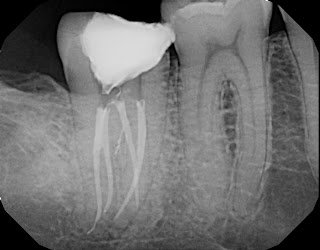

One of the biggest claims made regarding the GentleWave technique is “improved removal of organic matter” and creating a “higher standard of clean”. Evidence provided for this claim are usually images of more complex anatomy picked up when the tooth is obturated. The advocates call this “the thrill of the fill”.

However, the idea of cleaning and filling lateral canals and isthmuses is not unique to GentleWave. In our practice we have used both ultrasonic and sonic activation of irrigating solutions which has provided 3D cleaning and shaping of complex canal anatomy.

I have included several radiographic that demonstrate the “Thrill of the Fill” routinely seen at SSE using sonic activation of irrigating solutions. After our hands on demonstration with the GentleWave, I began putting aside radiographs after using sonic activation and found that the fill results were equally impressive.